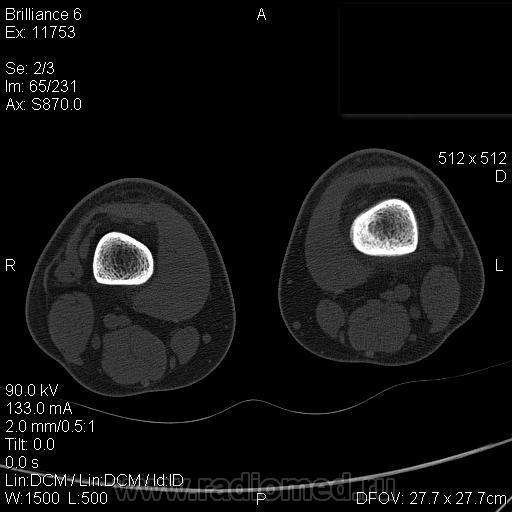

Мальчик 15 лет. Несколько месяцев назад начали беспокоить боли в коленных суставах. Травмы не было. Ребёнку был выставлен диагноз: болезнь Шлаттера, назначено лечение. На фоне лечения отмечалось значительное усиление болей, боли локализовались в левом коленном суставе. При дообследовании выявлена следующая рентгенологическая картина. Наши рентгенологи настаивают на срастающемся переломе. Но: 1) перелом без травмы? 2) бедро так не ломается

Да, на мой взгляд, состояние после обычного "травматического перелома" (трещина), не думаю, что имел место "патологический перелом", так как костная ткань "патологически изменена" минимально. "Перистальная реакция"локальная тоже есть, на КТ "локальная  зона склероза" - все это свидетельствует именно об этом. Хотя в памяти у меня хорошо отложился Ваш последний случай о локальном утолщении кортикального слоя, когда "яйца в гнезде" еще не было. То, что анамнестически "травмы не было" - ничего не значит. Вы, по всей видимости, тоже часто встречались с такими случаями, когда ребенок не акцентировал внимание на "травме", как таковой, хотя клиника есть, боль есть. Конечно, рентгенограммы - не дай бог - ни скиалогии, ни структуры.

В любом случае, мы посовещались и решили не рисковать. Завтра ребёнок идет на открытую биопсию.

Буквально заключение гистологов передать не могу (мой недочет, нужно было сразу выложить на сайтОй-ой-ой), но приблизительно помню - данных за специфический процесс нет, картина консолидирующегося перелома.

Так что, по всей видимости, это действительно был стресс-перелом. Который крайне редко встречается. Хоть статейку в журнал пишиУлыбаюсь.